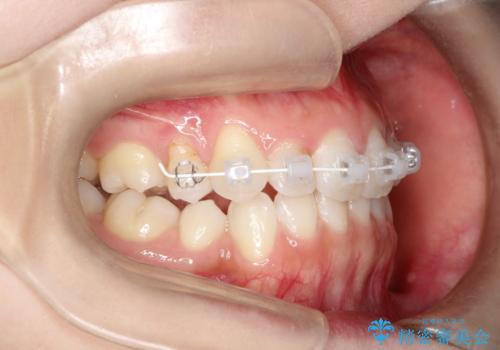

前歯の後戻りを部分矯正で整った歯並びへ

- 矯正治療後の上の前歯の後戻りを気にされて来院されました。

上の前歯のみにブラケットをつけて矯正治療を行いました。